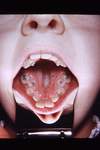

Erythema Multiforme

- Probably autoimmune; 50% pts had other infx

-

EM Minor: Target lesions of skin, assoc w/ HSV

- Mostly male, 20s-30s, self-limiting (2-6 wks)

- 20% recurrence, irreg lesions necrose/ulcer

-

EM Major: (Stevens-Johnsons Syndrome)

- Sick Patients, trigger often a med, 5M/yr

-

Toxic Epidermal Necrolysis (TEN)

- Old pts, tx in burn unit, sloughing of skin